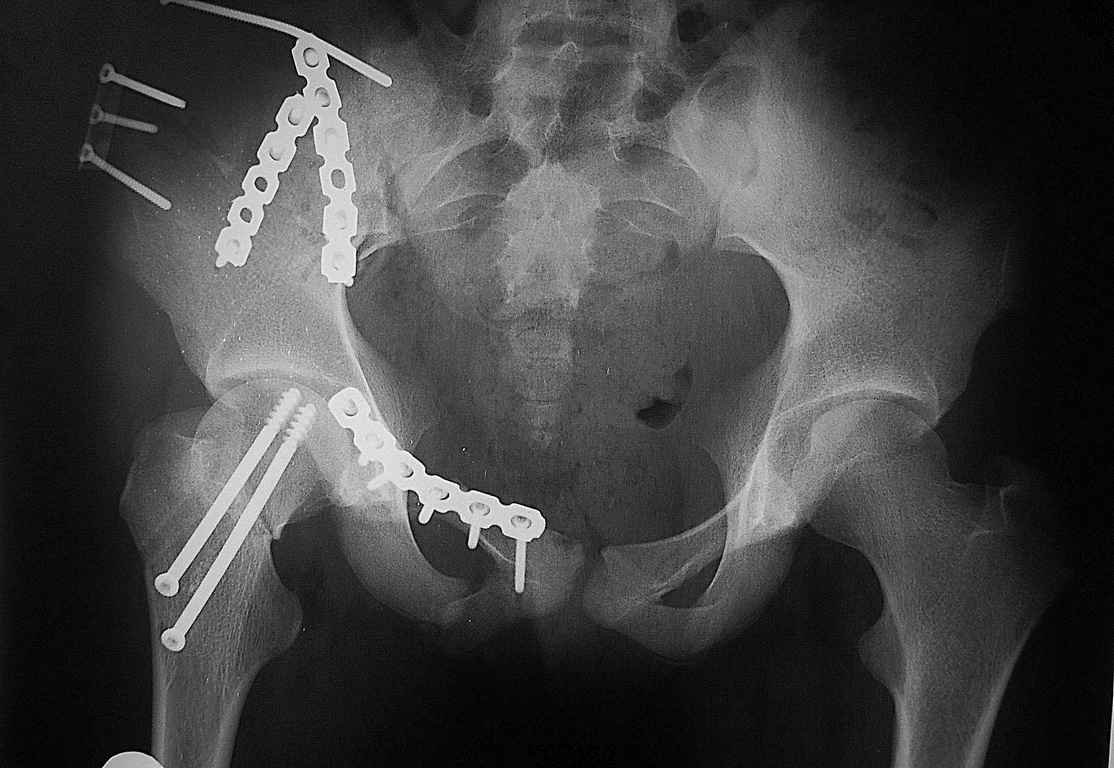

Уважаемый Алексей, на представленных Вами снимках имеется вертикально-нестабильное повреждение тазового кольца без повреждения вертлужной впадины. Учитывая это, а так же растущий возраст ребенка я бы выбрал аппарат внешней фиксации в виде кольцевой опоры, т.к. не смотря на оскольчатый перелом крыла в переднем отделе можно ввести минимум 2 стержня + 1-2 надвертлужно. Этого будет достаточно чтобы "зацепится", выполнить репозицию и дальнейшую фиксацию. Перелом шейки по моему лучше прооперировать 3 канюлированными винтами по АО.

Шейку срочно закрыто винтами.

Таз - подвздошным и падлобковым доступом раздельные рекострукционные пластины 4 штуки. Сплошную пластину как у взрослых нельзя (из-за роста придется доставать)